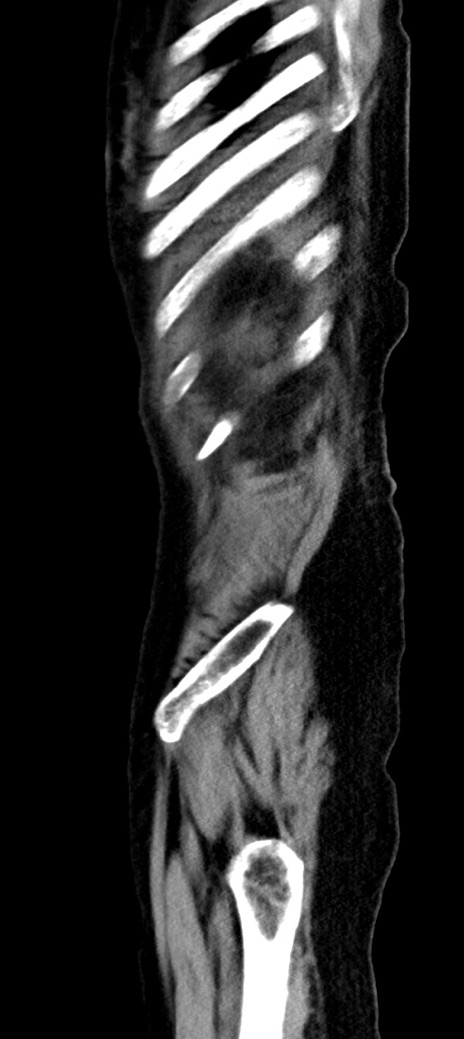

症例40(矢状断像)他院1日前

【症例】90歳代女性

【主訴】腹痛・嘔吐

【現病歴】 食欲低下、嘔吐があり昨日他院受診。肺炎と診断され入院となる。入院後より腹部全体に圧痛あり。胃管留置され経過みていたが、症状持続するため、

当院転院となる。

【既往歴】胸椎圧迫骨折、胆石症

【身体所見】腹部:中央に激痛あり、圧痛あり、反跳痛不明

【データ】WBC 17100、CRP 18.82